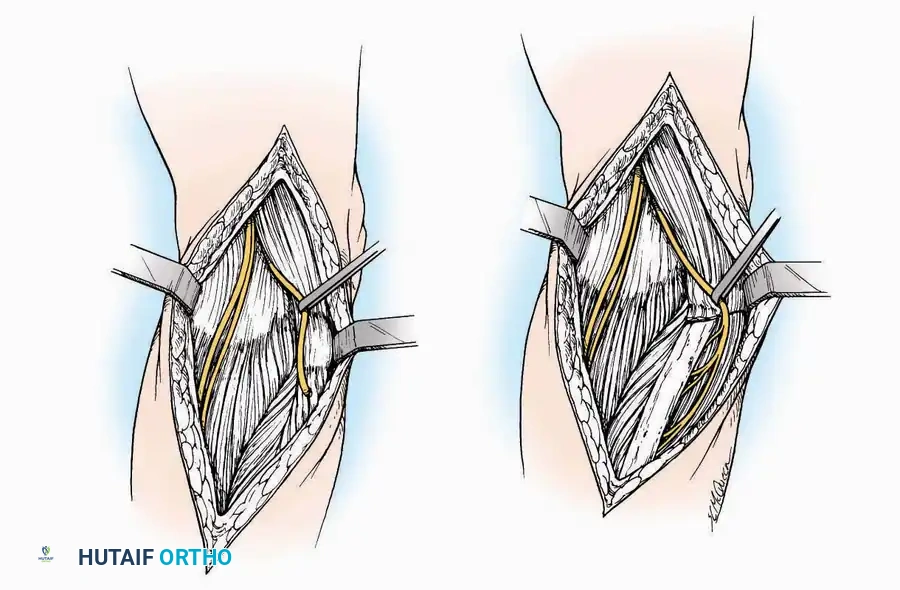

* Deep Dissection: Carry the dissection sharply through the subcutaneous tissue and superficial fascia directly to the joint capsule.

* Neurovascular Protection: Reflect the skin edges with meticulous care. Retract the dorsal digital nerves and vessels dorsally, and the plantar nerves and vessels plantarward.

* Capsulotomy: Open the capsule either transversely (for joint resection/arthrodesis) or longitudinally (for exploration), exposing the articular surfaces.